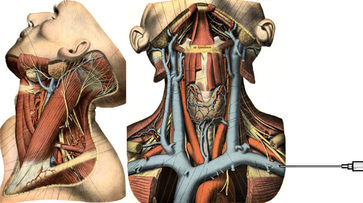

Diese Anforderungen treffen ausschließlich auf die proximale rechte Vena jugularis / Vena anonyma zu, die deshalb als Standardzugang verwendet werden sollte, zumal diese Punktion auch besonders einfach unter sonographischer Kontrolle erfolgen kann.

Die Vena jugularis/ Vena anonyma kann nach Yoffa zwischen medialem und lateralem Kopf des Musculus sternocleidomastoideus von ventral punktiert werden oder horizontal von lateral. Diese Methode wurde 1972 von den amerikanischen Herzchirurgen Garcia, Mispireta und Pinho nach ausführlichen anatomischen Präparationen als einfachster und ungefährlichster Zugang beschrieben. Das Zielgebiet, der Zusammenfluß von Vena jugularis und Vena subclavia zur Vena anonyma ist so groß, dass die Punktion auch ohne Sonographie immer beim ersten Stich gelingt.

Die in der Anästhesie verbreitete Punktion der distalen Vena jugularis ist komplikationsträchtig und sollte vermieden werden. Normalerweise liegt die Vena jugularis lateral der A. carotis.

Bei der schädelnahen Punktion muß der Kopf nach links gedreht werden, weil sonst das Kinn im Weg ist. Dadurch rotiert die Vene vor die Arterie und das Lumen wird schlitzförmig.

Vor der Einmündung in die Vena anonyma macht die Jugularvene einen Knick von 45 Grad nach dorsal. Diatator, Einführschleuse und Katheter stoßen dort an der Venenvorderwand an und erzeugen Intimaläsionen, die bei 30% der Patienten später zur Thrombose führen.

Darüberhinaus geht der Katheter durch die ganze Breite des Musculus sternocleidomastoideus. Dies führt zu einer rein/raus-Bewegung des Katheters bei jedem Schlucken und jeder Kopfbewegung. Das begünstigt einerseits das Einwandern von Hautkeimen in den Punktionskanal, andererseits werden Fibrinablagerungen auf der Katheteroberfläche an der Punktionsstelle abgestreift. Dadurch kommt es zu einer Akkumulation von Fibrin und thrombotischem Material an der Venenwand und um den Katheter.